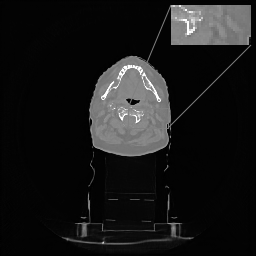

In Tables 1 and 2 we report these metrics on thorax CT data for straight and rotated patient orientation respectively, and the corresponding box plots are provided in Figures 1 and 2. Since the classical reconstruction methods such as FBP and TV are not trained on specific patient orientation, they are robust to rotations by design and are ommited in the second comparison. On the straight data, we observe that LIRE and LIRE+ noticeably outperform all the baselines. LIRE+ is able to achieve LIRE level of performance using only 99 iterations out of 1212. Full version of LIRE+ with 12 iterations gives a small performance improvement over LIRE. \partialU-net, while being fast, cannot match the reconstruction quality achieved by LIRE/LIRE+, even though it has more parameters. On the rotated data, we note that only LIRE+ is able to maintain the reconstruction quality thanks to the rotationally-equivariant primal cells, while all alternative models suffer from various amounts of performance degradation. It is wothwhile to note that the performance degradation is more pronounced in the learned post-processing baselines (Uformer and U-net), while learned iterative schemes seem to be more robust.

Examples of axial image slices of a ground truth image and the corresponding reconstructions with \partialU-net, LIRE and LIRE+ are presented in Fig. 3 with the respective difference maps in Fig. 4. Coronal view is provided in Fig. 5 and Fig. 6. For the image samples the HU range equals (-1000, 800) and (-1350, 150) for the ROI, while for the difference maps HU range equals (-1000, 800) and (-200, 200) for the ROI. From these examples we can see that LIRE+ gives sharper images with better HU calibration, while \partialU-net appears to slightly blur lung fissures. The difference maps suggest that particularly for LIRE+ image noise plays a large role in the image quality metrics.

Refer to caption

(a)

(b)

(c)

(d)

Figure 5: (a) Coronal slice of Thorax CT, HU range=(-1000, 800) and (-1350, 150) for ROI, (b) \partialU-net, (c) LIRE, and (d) LIRE+ 12 it.